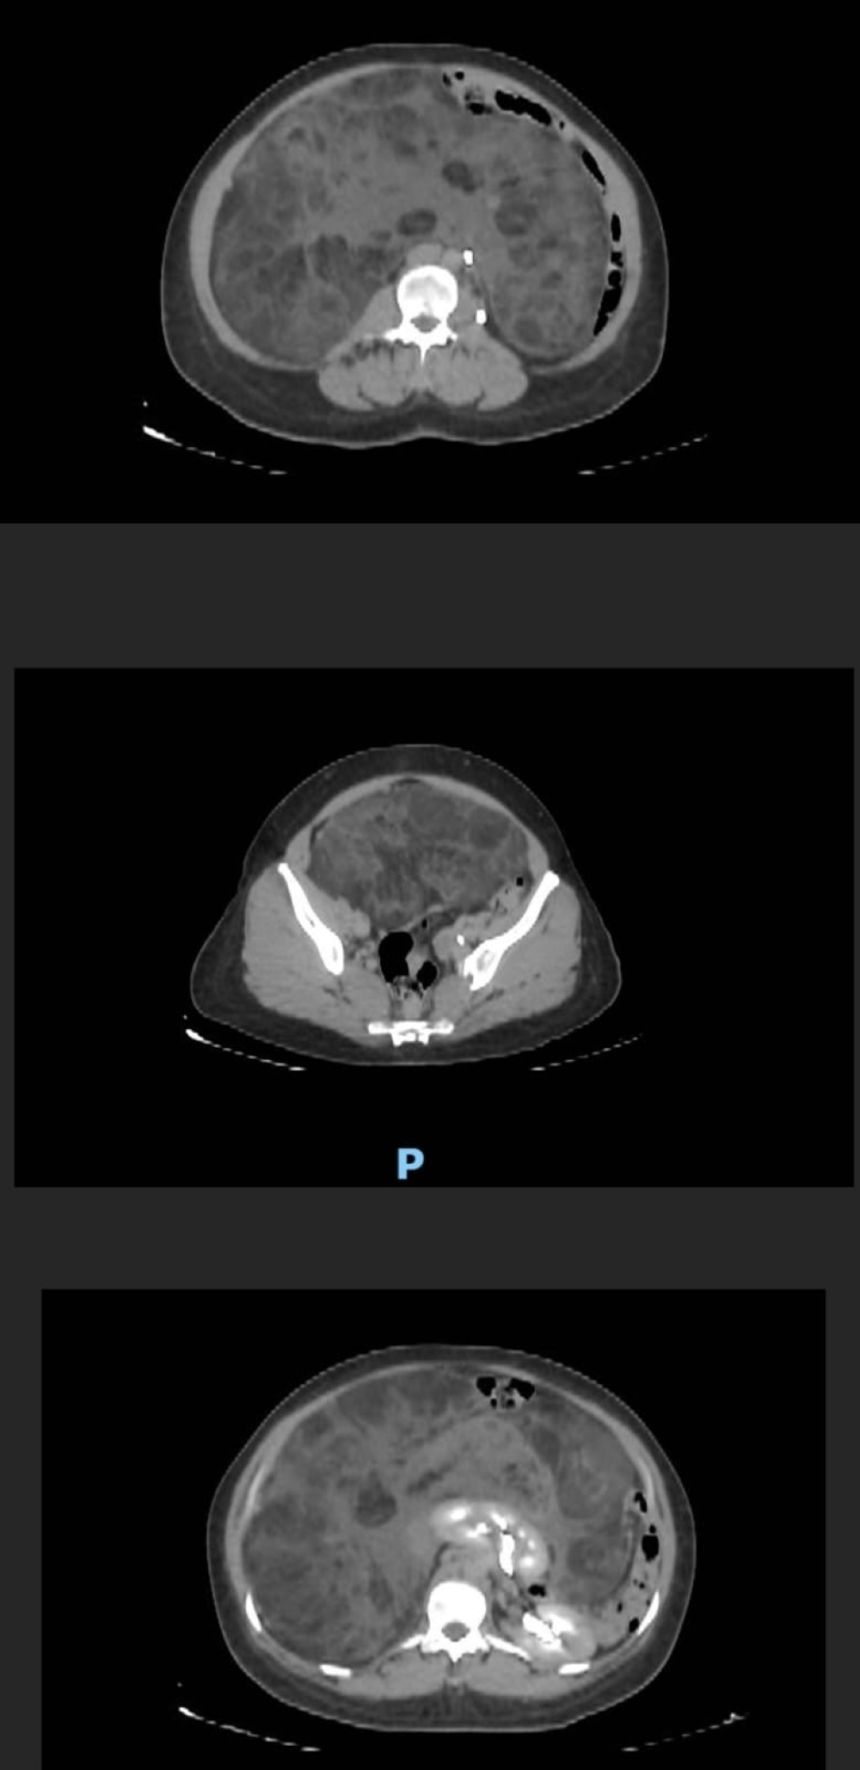

وأوضحت المدينة بأن الفريق الطبي للحالة بقيادة استشاري ورئيس وحدة جراحة أورام الجهاز العلوي والمناظير د.عبدالعزيز الربيع باشر الحالة بالفحص السريري وعمل الأشعة، تبين على إثرها وجود ورم (Sarcoma) نادر يضغط على الأعضاء الداخلية للتجويف البطني، يصل وزنه 9 كجم وبحجم ويصل إلى 45 سم كان يغطي كامل التجويف.